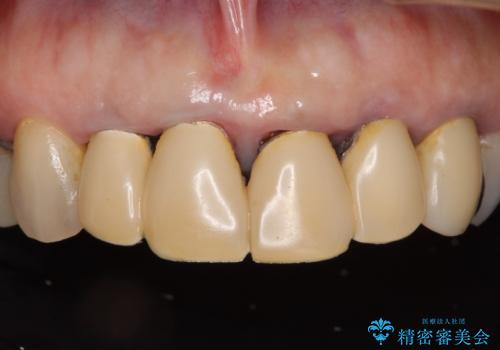

変色した前歯のクラウン オールセラミッククラウンにより審美歯科治療

クラウンと歯の縁も合っておらず、汚れが溜まりやすい環境であったため、前歯2歯のクラウンをオールセラミッククラウンにて再補綴することとしました。

下顎前歯の部分矯正に半年ほどかかってしまい、少し期間は長いものとなりましたが、上下ともに前歯がきれいに整い、患者様には大変満足していただきました。